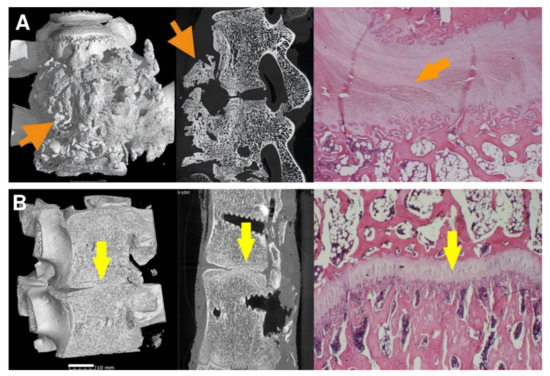

3.4. Micro-CT

3.5. Histology